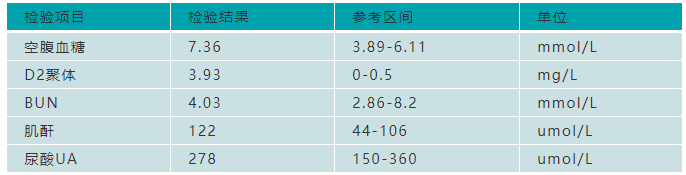

2020年12月1日以“低血糖”收住内分泌科,查即刻血糖5.4mmol/L。

2020年12月2日,检测空腹血糖2.8mmol/L,餐后2小时血糖2.48mmol/L。

胰岛素释放试验(0-60-120-180min):43.43-505.5-108.3-24.7uU/ml(参考区间:空腹胰岛素:2.6-24.9uU/ml),胰岛素释放指数1.11。

一般在血糖很低的时候,理论上胰岛素的分泌会相对减少,而该患者血糖在1.0mmol/L左右时,胰岛素基础水平为43.43uU/ml,远远超出基础胰岛素分泌水平。在血糖没有明显升高时,胰岛素水平能到达500左右,而胰岛素释放指数1.11,符合Whipple三联征,可以考虑胰岛β细胞内分泌功能异常。

患者术后监测检验结果:

患者血糖水平恢复,各项指标也趋于正常。在随后的门诊随访中血糖测定值为5.79mmol/L,手术治疗有效。